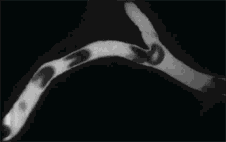

△ 免疫细胞在组织中快速穿梭

这是到目前为止,对人体温度高能促进免疫力的提升、快速恢复机体健康最明确的研究结果。